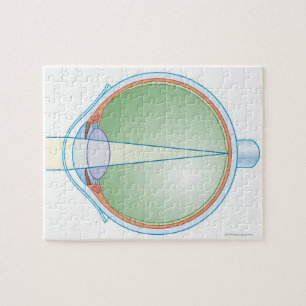

Impressão Em Tela Anatomia do crânio, do globo ocular e de artéria

PreçoR$ 712,00

Produto oficialmente licenciado